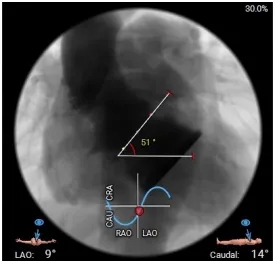

瓣环水平夹角51°